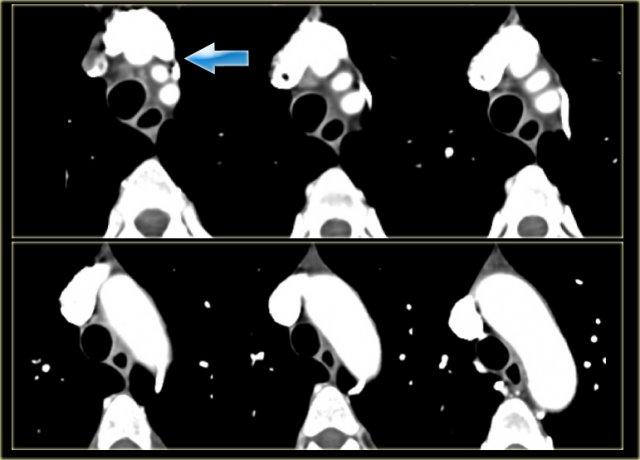

Double Arch with Atretic Segment

Occasionally the double arch can have an atretic segment.

You should not confuse it for a right arch.

The left arch is just very small and there is still a four vessel sign.

On the left a dominant right arch and a small left arch.

The atretic segment is marked by the arrow.

Notice the four vessel sign.

On a posterior view the interruption is nicely demonstrated.

Remember that there is still a ring, so there is still obstruction.

Another case on the left.

Do not call this a right arch.

It still is a double arch and there is a atretic fibrotic segment on the posterior side of the left arch, that completes the ring.

Same patient.

Always look at the airways.

On the recoonstruction the impression on the trachea is better appreciated.